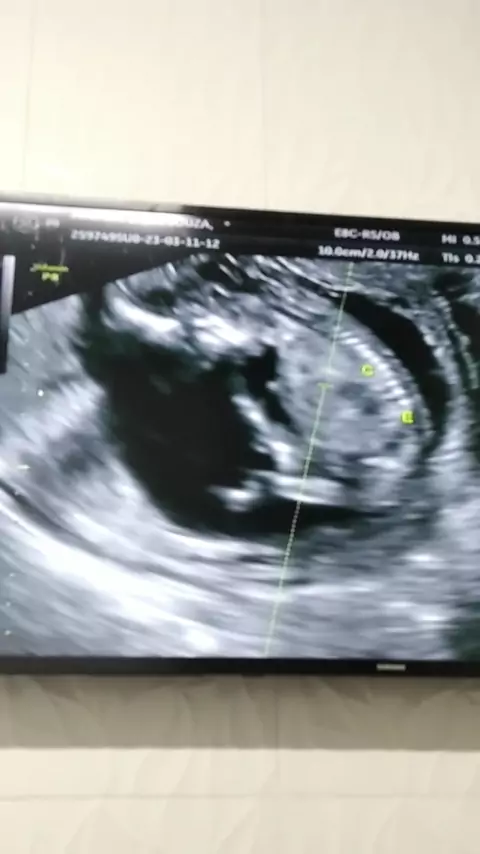

#todos #gestaçao #bebêarcoíris #gravidinha